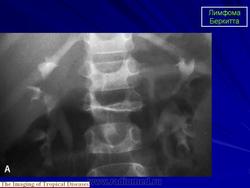

В диагностике лимфомы Беркитта гистологическое исследование опухоли играет большую роль. Под микроскопом видно множество мелких темных лимфоцитов периодически перемежается крупными «звездами» - макрофагами, которые пытаются фагоцитировать опухолевые клетки ( так называемое « звездное небо» ). Другими диагностическими методами исследования, в зависимости от предполагаемых очагов локализации опухоли, являются: двусторонняя биопсия и аспирация костного мозга; рентгенография органов грудной клетки, брюшной полости и таза, реже - двусторонняя лимфоангиография нижних конечностей и таза; рентгенография костей, биопсия печени.

Продолжение.

Приложения:

11.berkita.slayd13.jpg